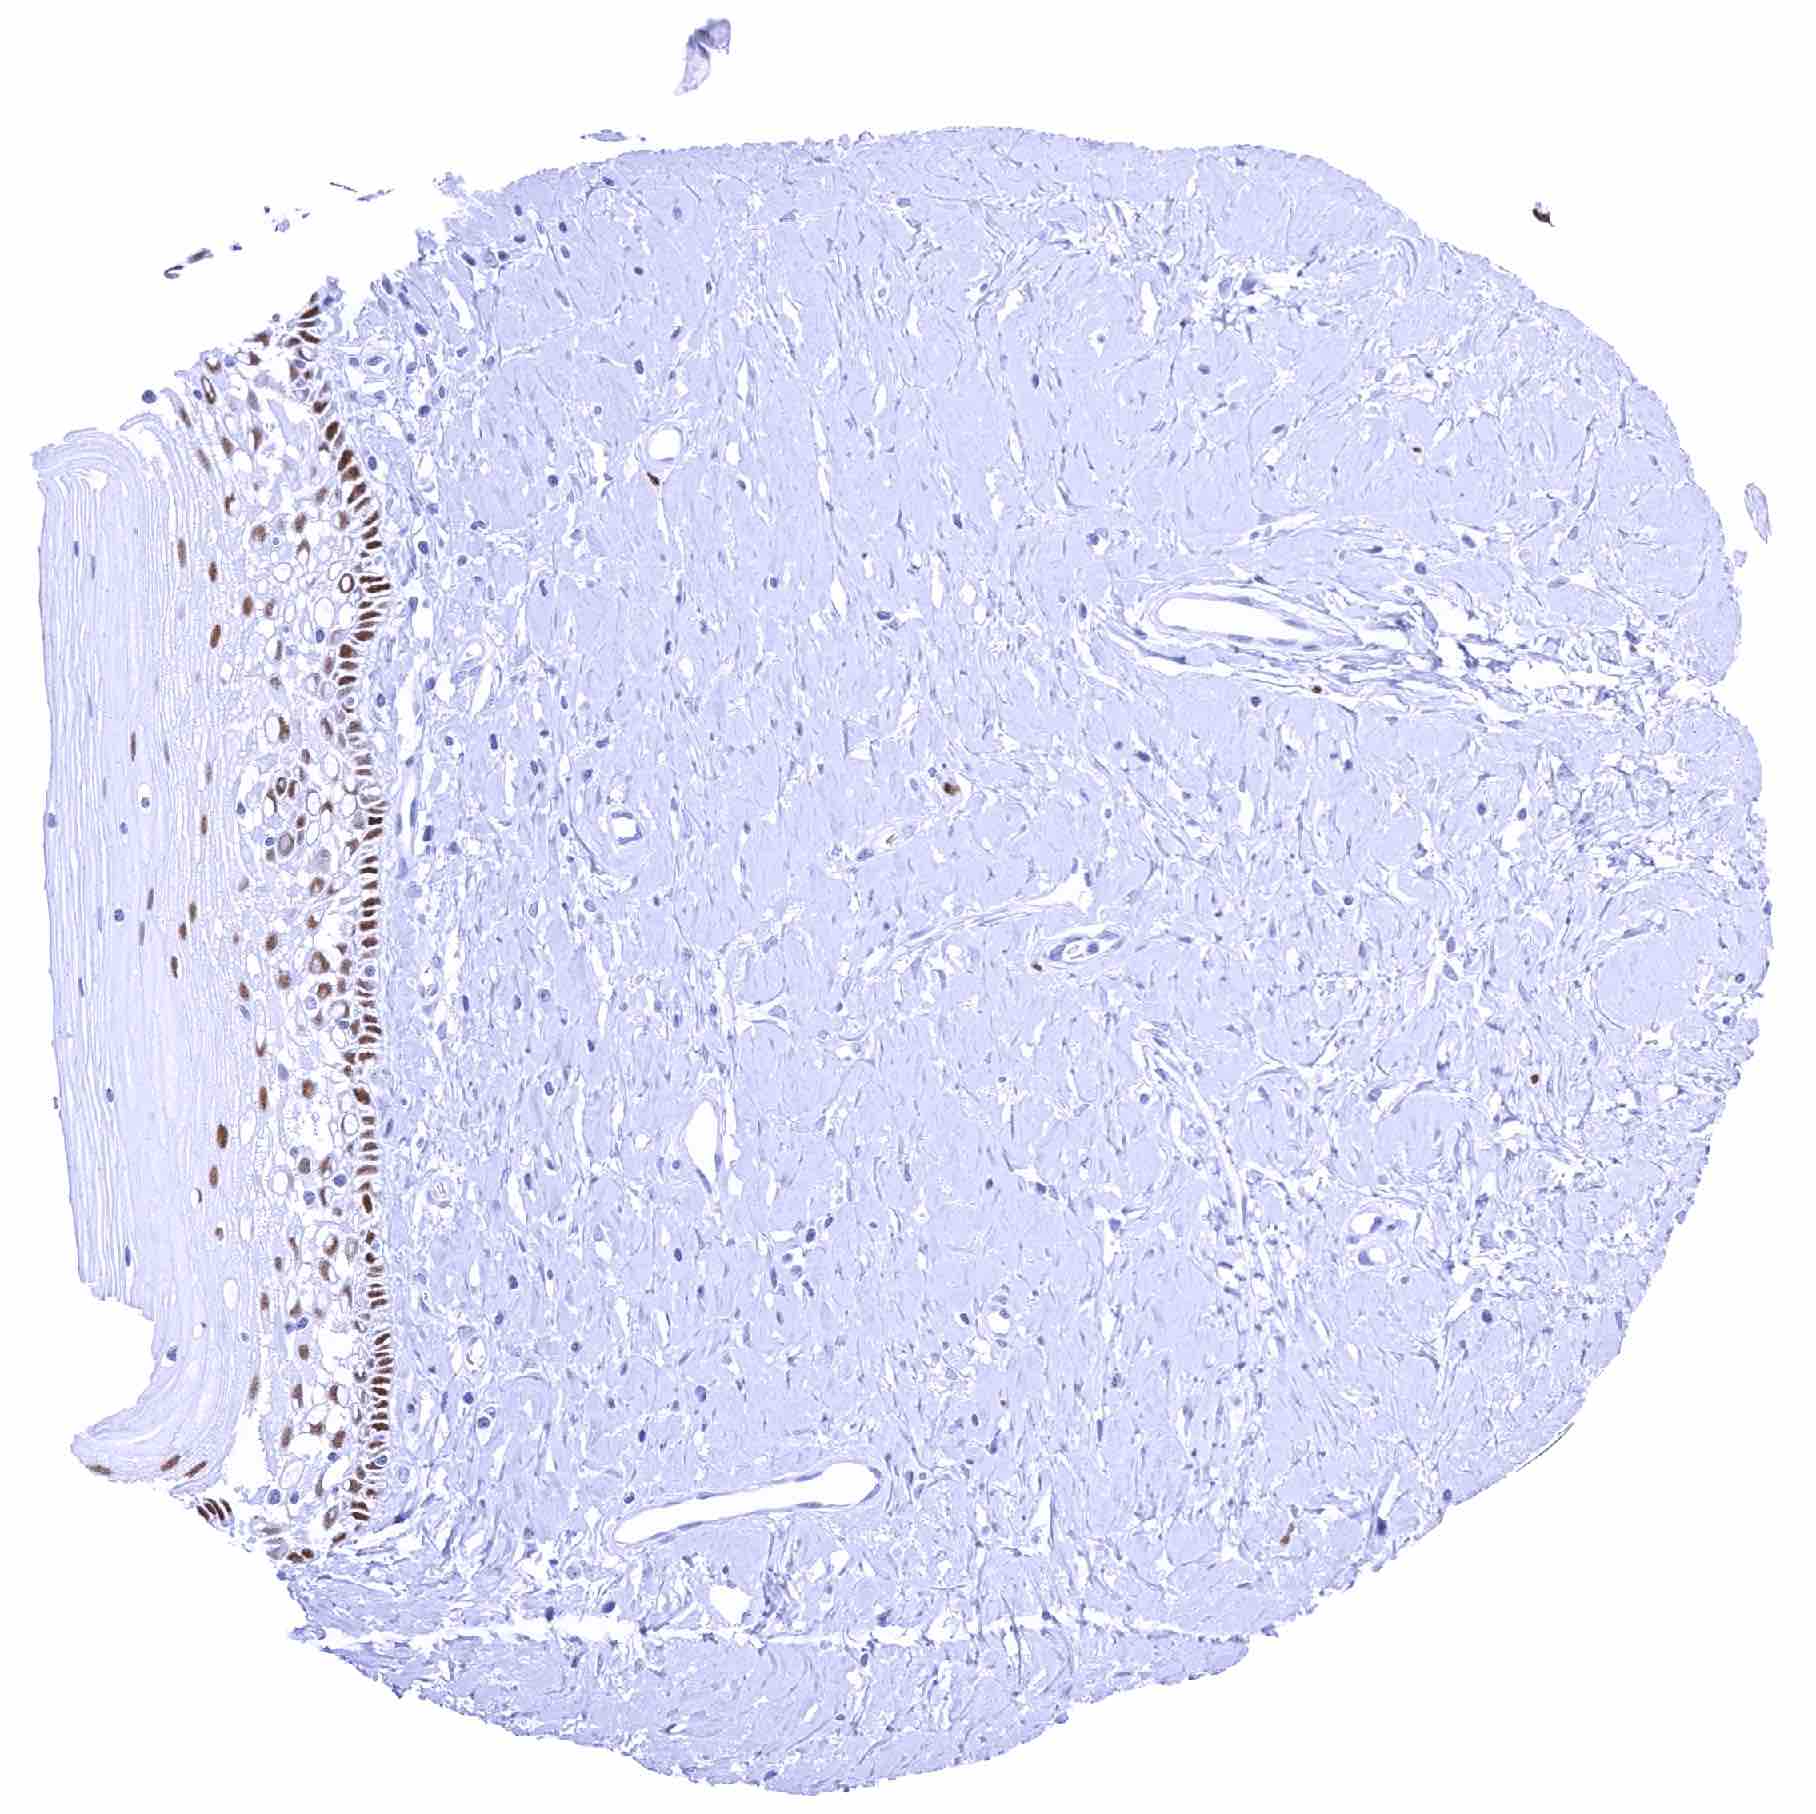

Uterus, ectocervix

Uterus, ectocervix (2)